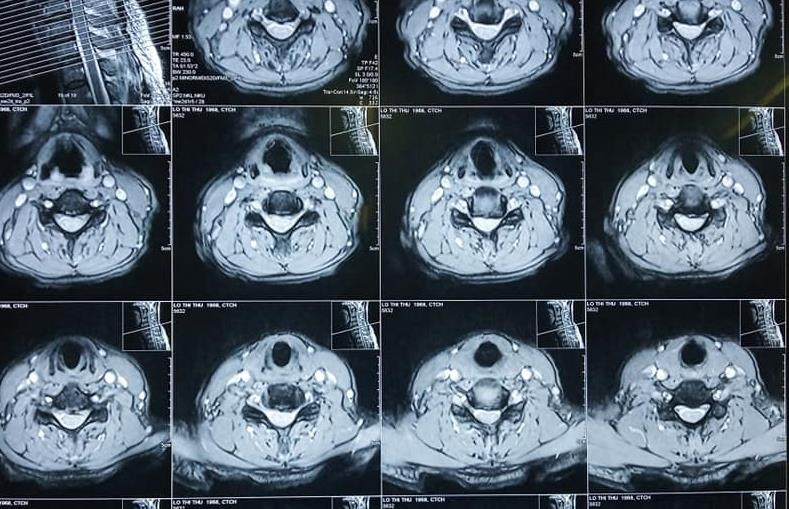

Bệnh nhân Lô Thị Thư ở Nghĩa Đàn, Nghệ An được chuyển tuyến đến Bệnh viện Chấn thương Chỉnh hình Nghệ An trong tình trạng sức khỏe yếu, đau đầu nhiều, sưng nề vùng mặt, đau hạn chế vận động cột sống cổ, tê bì hai tay, không ngồi dậy được.